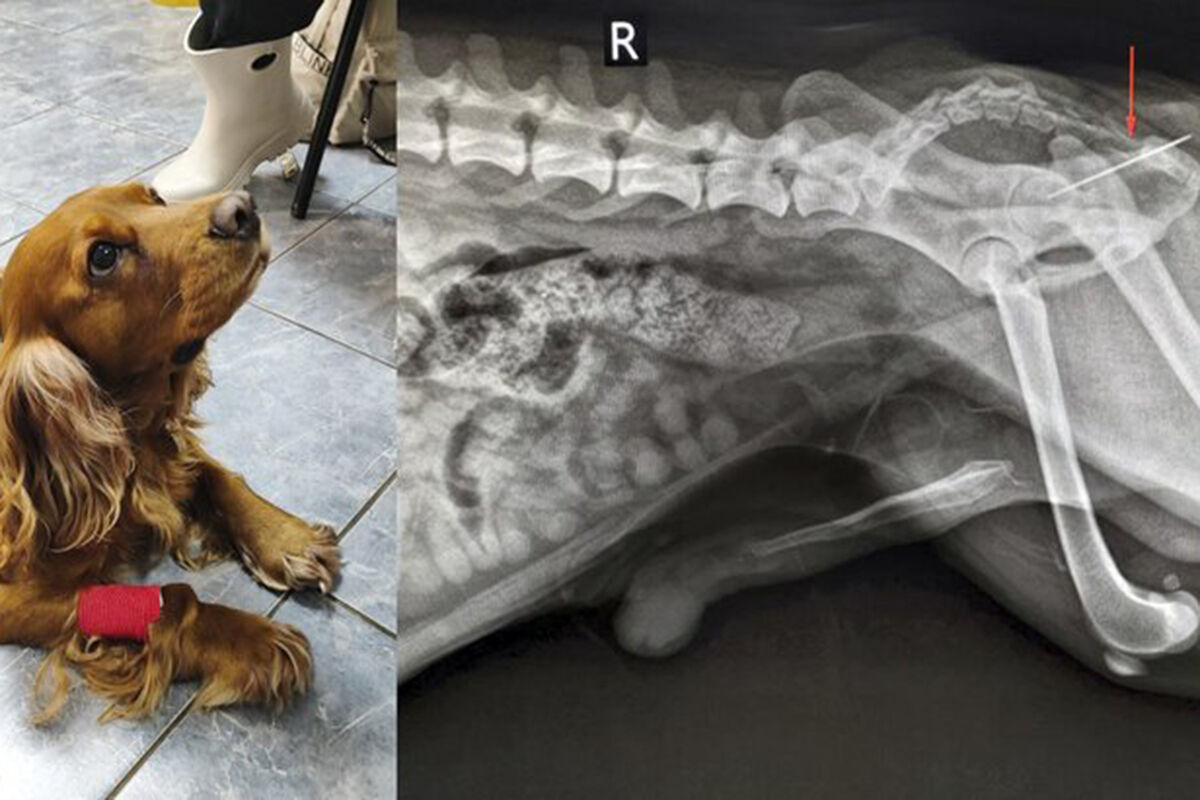

В ветклинике Коптево специалисты спасли собаку породы кокер-спаниель по кличке Вольт, которая проглотила швейную иглу. Об этом «Москве 24» рассказали в столичной госветслужбе.

В ведомстве уточнили, что ее хозяева заметили, что она испытывает дискомфорт, когда хочет в туалет.

«При осмотре терапевт Анна Кубатина заметила, что из заднего прохода Вольта торчит швейная нитка. Пациента срочно отправили на рентген», – добавили в пресс-службе.

Врачи установили, что за ниткой тянулась и игла, которая застряла в прямой кишке. Хирург Евгений Бахтин и анестезиолог Светлана Дорожкина провели операцию по извлечению иглы, после этого питомца отпустили домой.